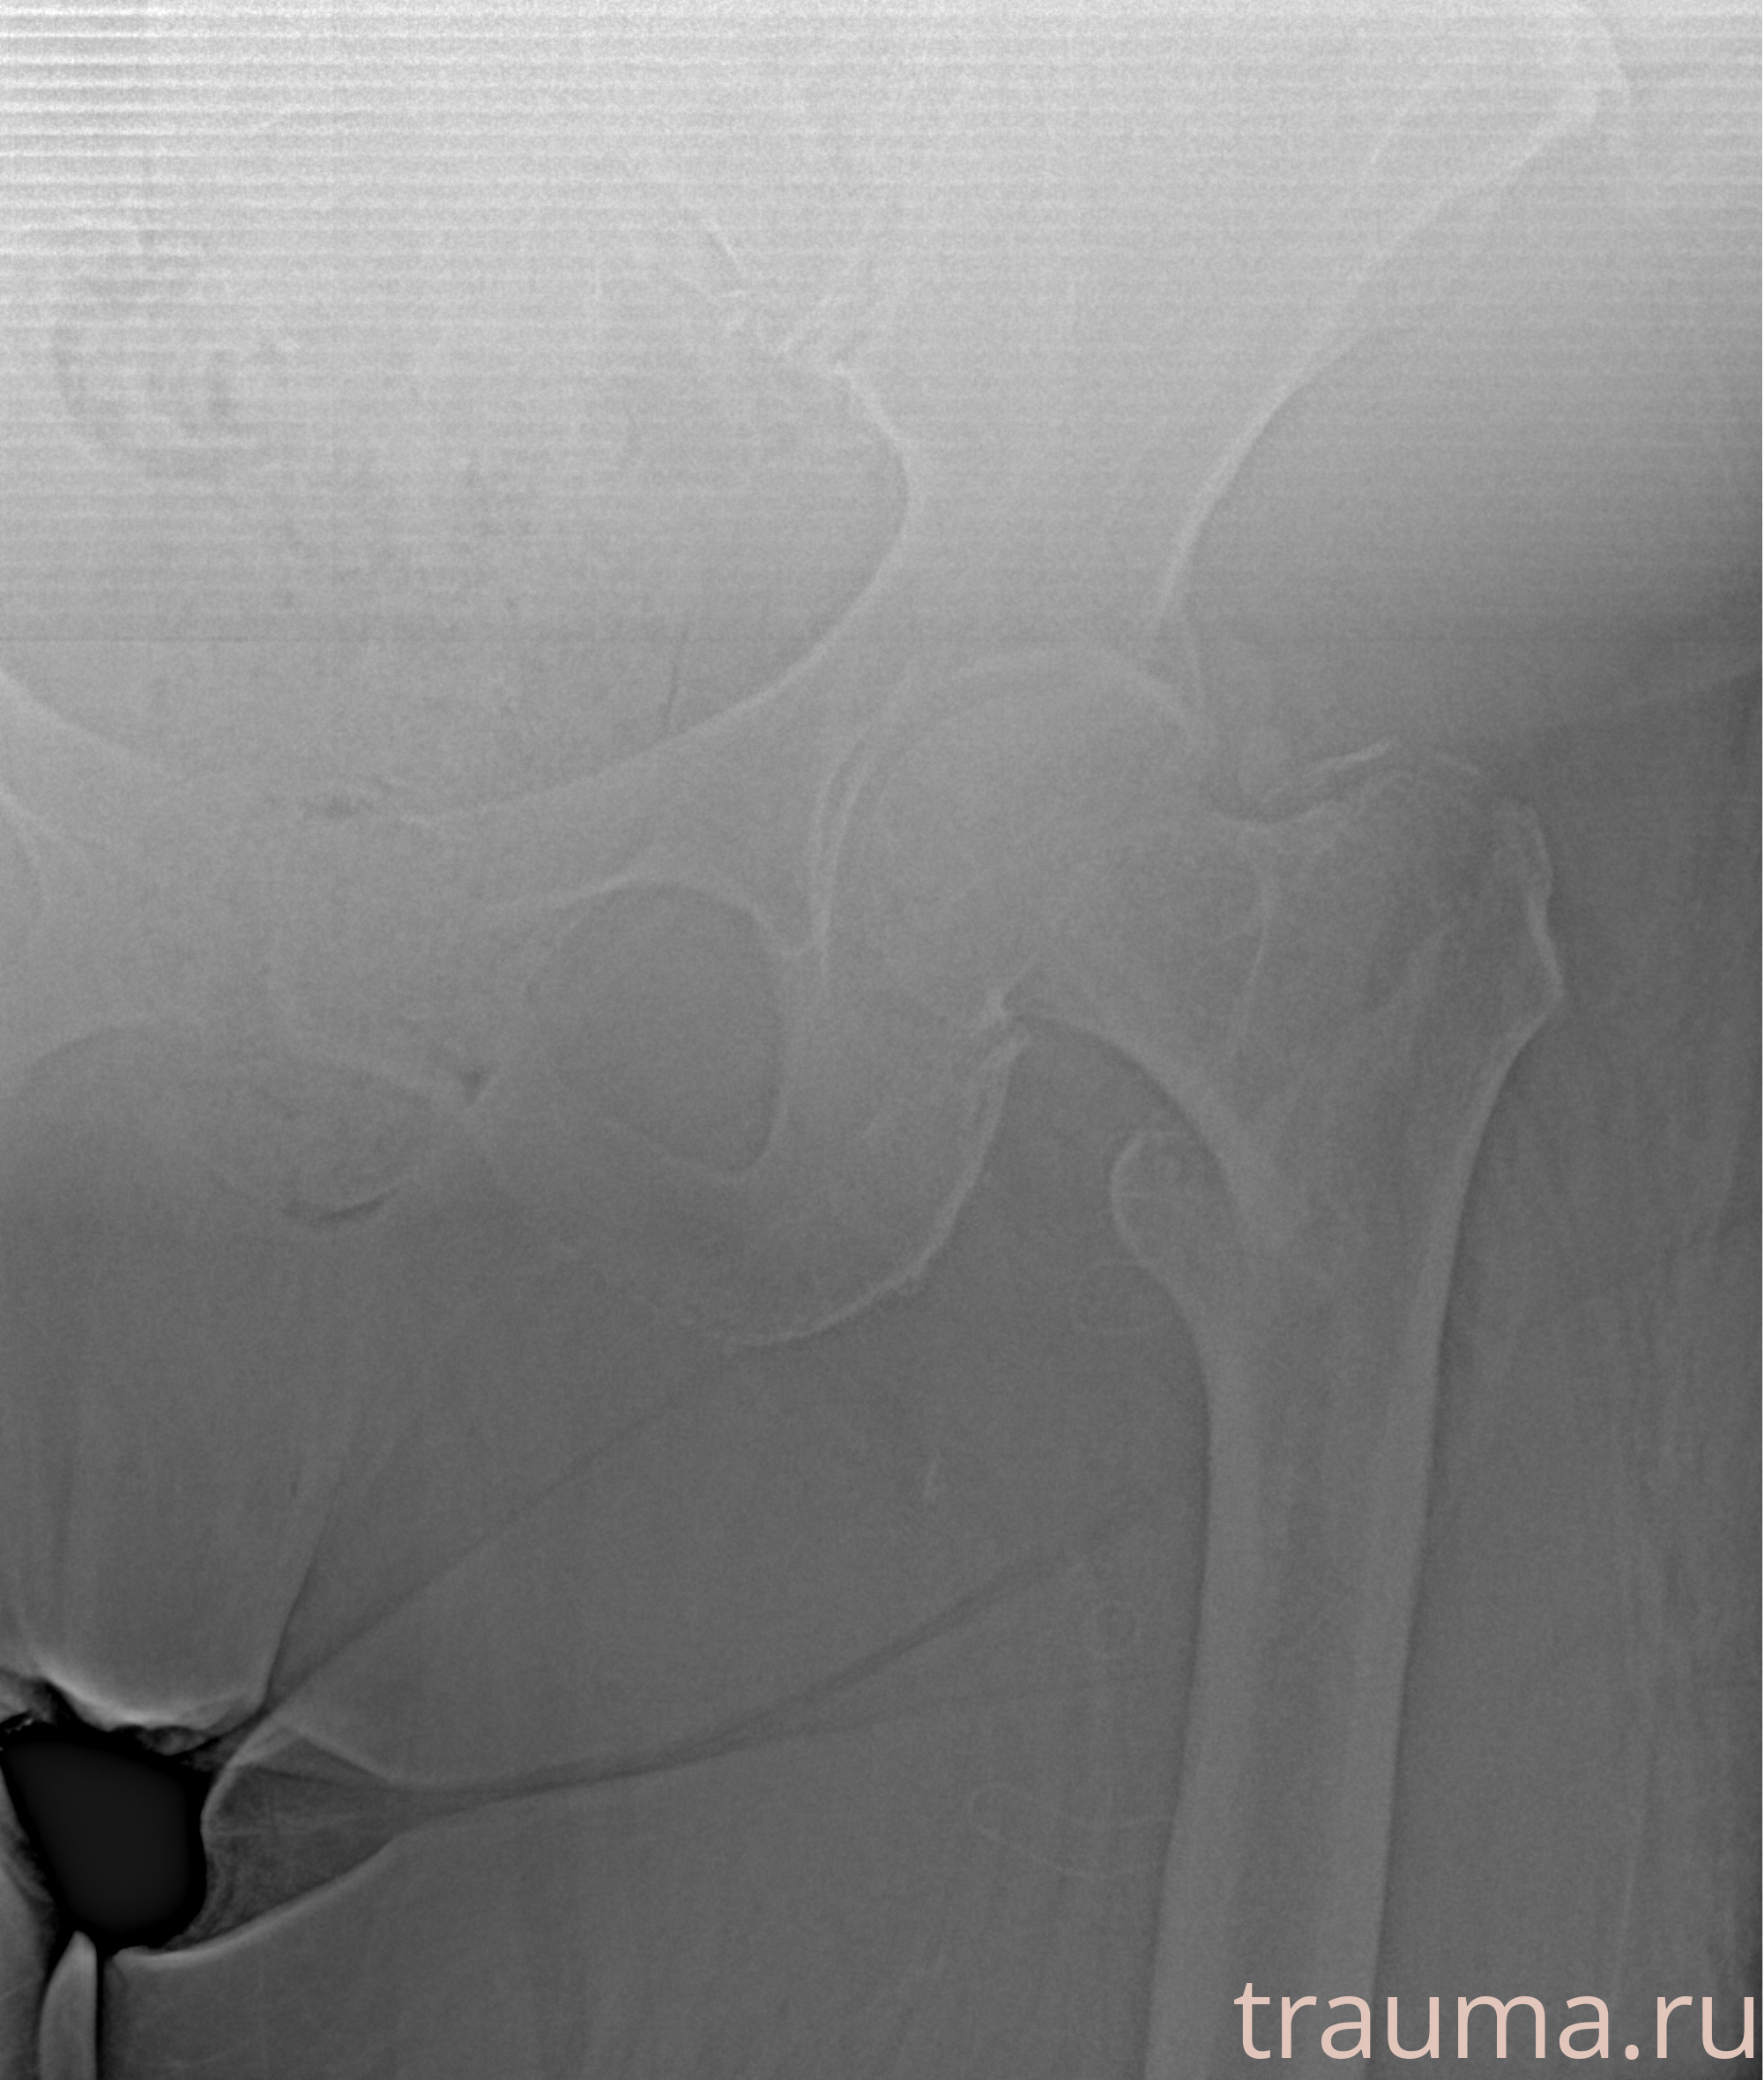

Рентгенограммы

Рентген на дому: по вашему адресу приезжает врач-рентгенолог, травматолог-ортопед с мобильным рентгеновским аппаратом, проводит диагностику травмы или заболевания, делает необходимые рентгенограммы, дает рекомендации по дальнейшему лечению. Получить качественные снимки в домашних условиях возможно благодаря уникальной методике, разработанной МосРентген Центром для института  Склифосовского